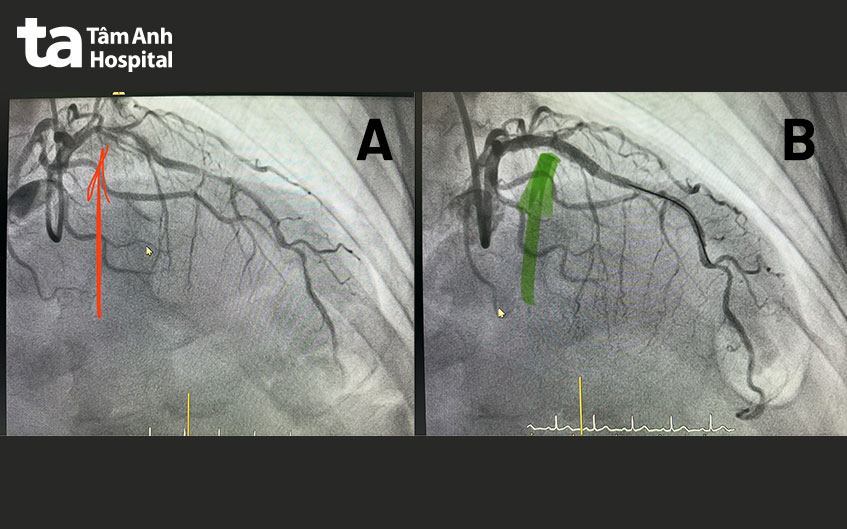

Ê kíp tiến hành nong mạch đặt stent cho ông Phát. Vì thủ phạm chính gây đau thắt ngực là đoạn liên thất trước bị tái hẹp nên bác sĩ ưu tiên làm trước nhánh này. Nhờ kỹ thuật ULC-PCI (can thiệp mạch vành với lượng cản quang tối thiểu) kết hợp hệ thống siêu âm trong lòng mạch – IVUS, bác sĩ đưa ống thông đến mạch vành bị hẹp nghẽn mà không cần bơm thuốc cản quang, tiếp đến nong bóng để giúp mạch vành giãn tối ưu.

Nhờ đó, thuận lợi đưa stent mới (kích thước 3.5 x 26 mm) vào, bung rộng stent ép chặt chỗ xơ vữa và mở thông lòng mạch. Dòng máu nuôi tim được khơi thông.